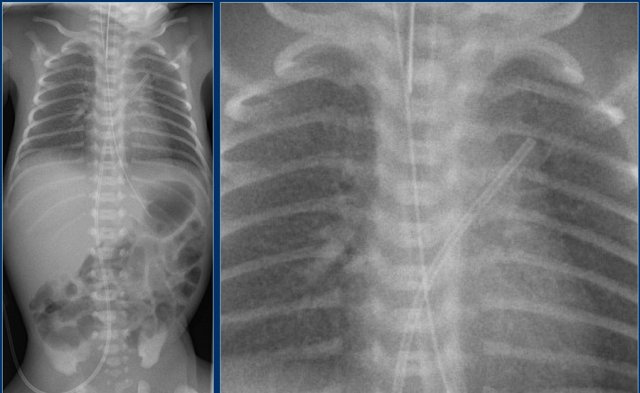

Umbilical artery line (2)

First study the images.

Then continue reading.

The findings are:

1. Umbilical artery line in a good high position.

2. Malposition of umbilical vein line in right portal vein.

3. Skin folds over right basal thorax, which should not be mistaken for a pneumothorax. They typically do not follow anatomical borders.